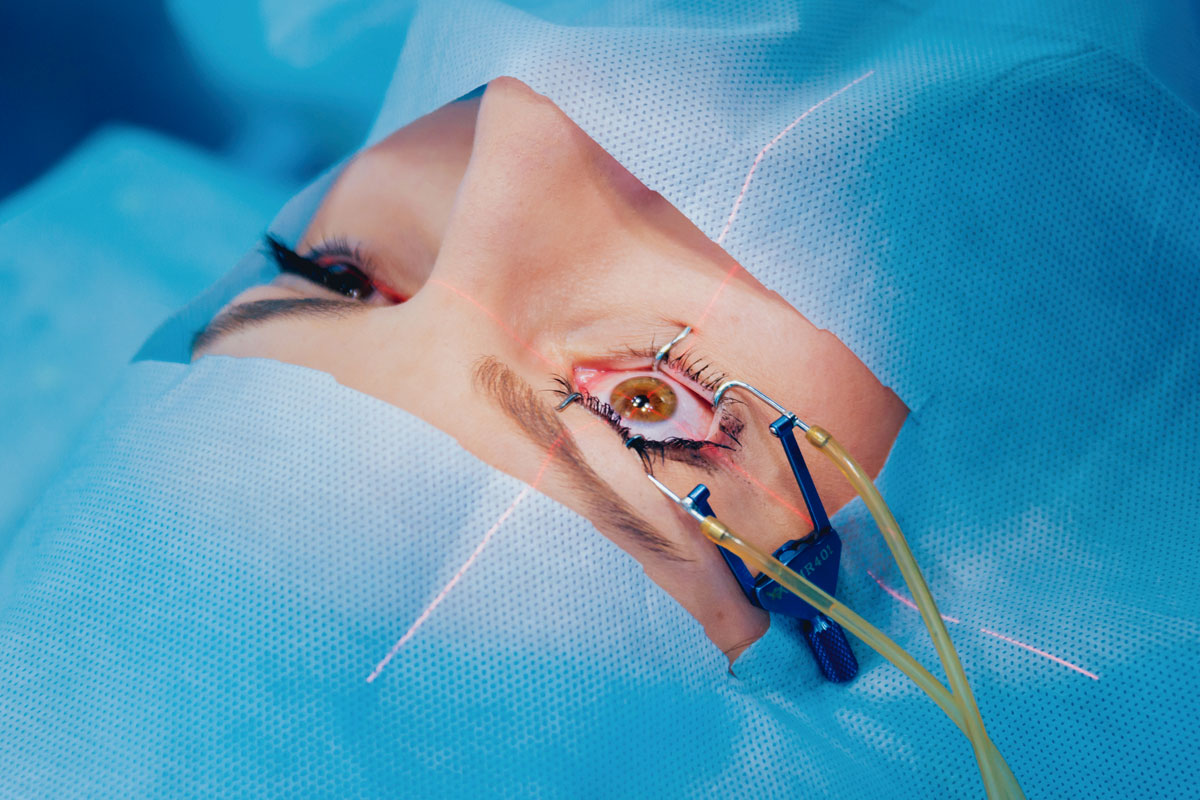

Read moreDetailsRiesgos retinianos en la miopía y la cirugía LASIK

Por Liz Hunter, editora sénior Enfoques para la detección y el tratamiento de las degeneraciones retinianas....